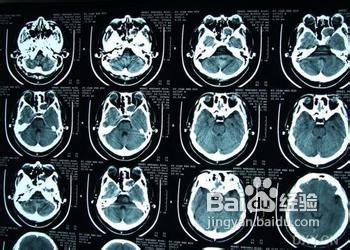

1、鼻腔检查:鼻腔外侧壁向中线移位;

4、囊肿自行溃破,囊液经鼻窦口流出所致自发间隙性清亮鼻溢。鼻塞、流涕、嗅觉减退;

5、眼部表现囊肿侵犯眶内所致。导致眼球移位,流泪、复视、视力障碍等。

1、低温等离子消融术治疗法是将等离子低温热效应直接作用于病变组织,无痛苦,在小范围内实现高热,产生凝固,使病变组织坏死,进而脱落达到去除病变的目的。消融过程仅需几分钟,术中不出血;对鼻黏膜损伤小,能最大程度恢复患者的嗅觉等生理功能,消除。